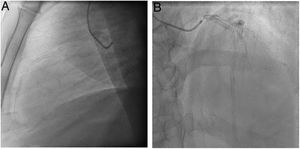

Caso clínicoPaciente varón de 57 años de edad, sin alergias medicamentosas conocidas, con antecedentes patológicos de hipertensión arterial, dislipidemia y diabetes mellitus tipo 2, afecto de cardiopatía isquémica crónica con enfermedad arterial coronaria de 3 vasos. A pesar de tratarse de un paciente joven, diabético y con enfermedad arterial coronaria de 3 vasos, fue tratado inicialmente mediante intervencionismo coronario percutáneo en 2007, con implante de SF en segmento medio de DA, y stents convencionales en arterias primera diagonal, circunfleja proximal y segunda marginal, en controversia con las indicaciones de las guías actuales. Dos años después, ante la reaparición de angina progresiva, se repitió la coronariografía, que mostró RIS severo en DA, tratado con nuevo implante de 3 SF en segmentos medio y distal. En 2021 consultó nuevamente por angina de esfuerzo, realizándose una nueva coronariografía que mostró enfermedad arterial coronaria de 2 vasos: RIS severo en DA (fig. 1A y B) y múltiples lesiones severas en la arteria coronaria derecha. Una ecocardiografía realizada en ese momento presentó disfunción ventricular moderada (FEVI 42%), así como un pequeño aneurisma apical. El caso fue presentado en sesión médico-quirúrgica, siendo aceptado para cirugía de revascularización coronaria.

La evolución clínica fue buena, con extubación precoz a las 6h, sin necesidad de fármacos inotrópicos. La radiografía de tórax mostró leves signos de insuficiencia cardiaca, con buena respuesta a diuréticos. Se inició antiagregación con AAS a las 24h, y anticoagulación con acenocumarol desde las 48h postoperatorias. El ECG postoperatorio mostró un RS a 90lpm, con bajo voltaje y supradesnivel del ST de V2-V5, no presente en el ECG preoperatorio, con posterior resolución (fig. 5 A y B). El pico máximo de troponina fue de 1.545pg/ml. Los niveles de CK y troponinas al alta fueron de 55u/l y 1.148,4pg/ml, respectivamente. Una ecocardiografía realizada antes del alta mostró VI no dilatado, con motilidad global moderadamente reducida (FE 38%), con acinesia extensa en segmentos septoanterior medio y apical, y leve hipocinesia inferoapical y apical. El paciente fue dado de alta a los 10 días de la intervención. En el seguimiento a 4 meses el paciente no presenta clínica de dolor torácico, manteniéndose en CF I-II de la NYHA.